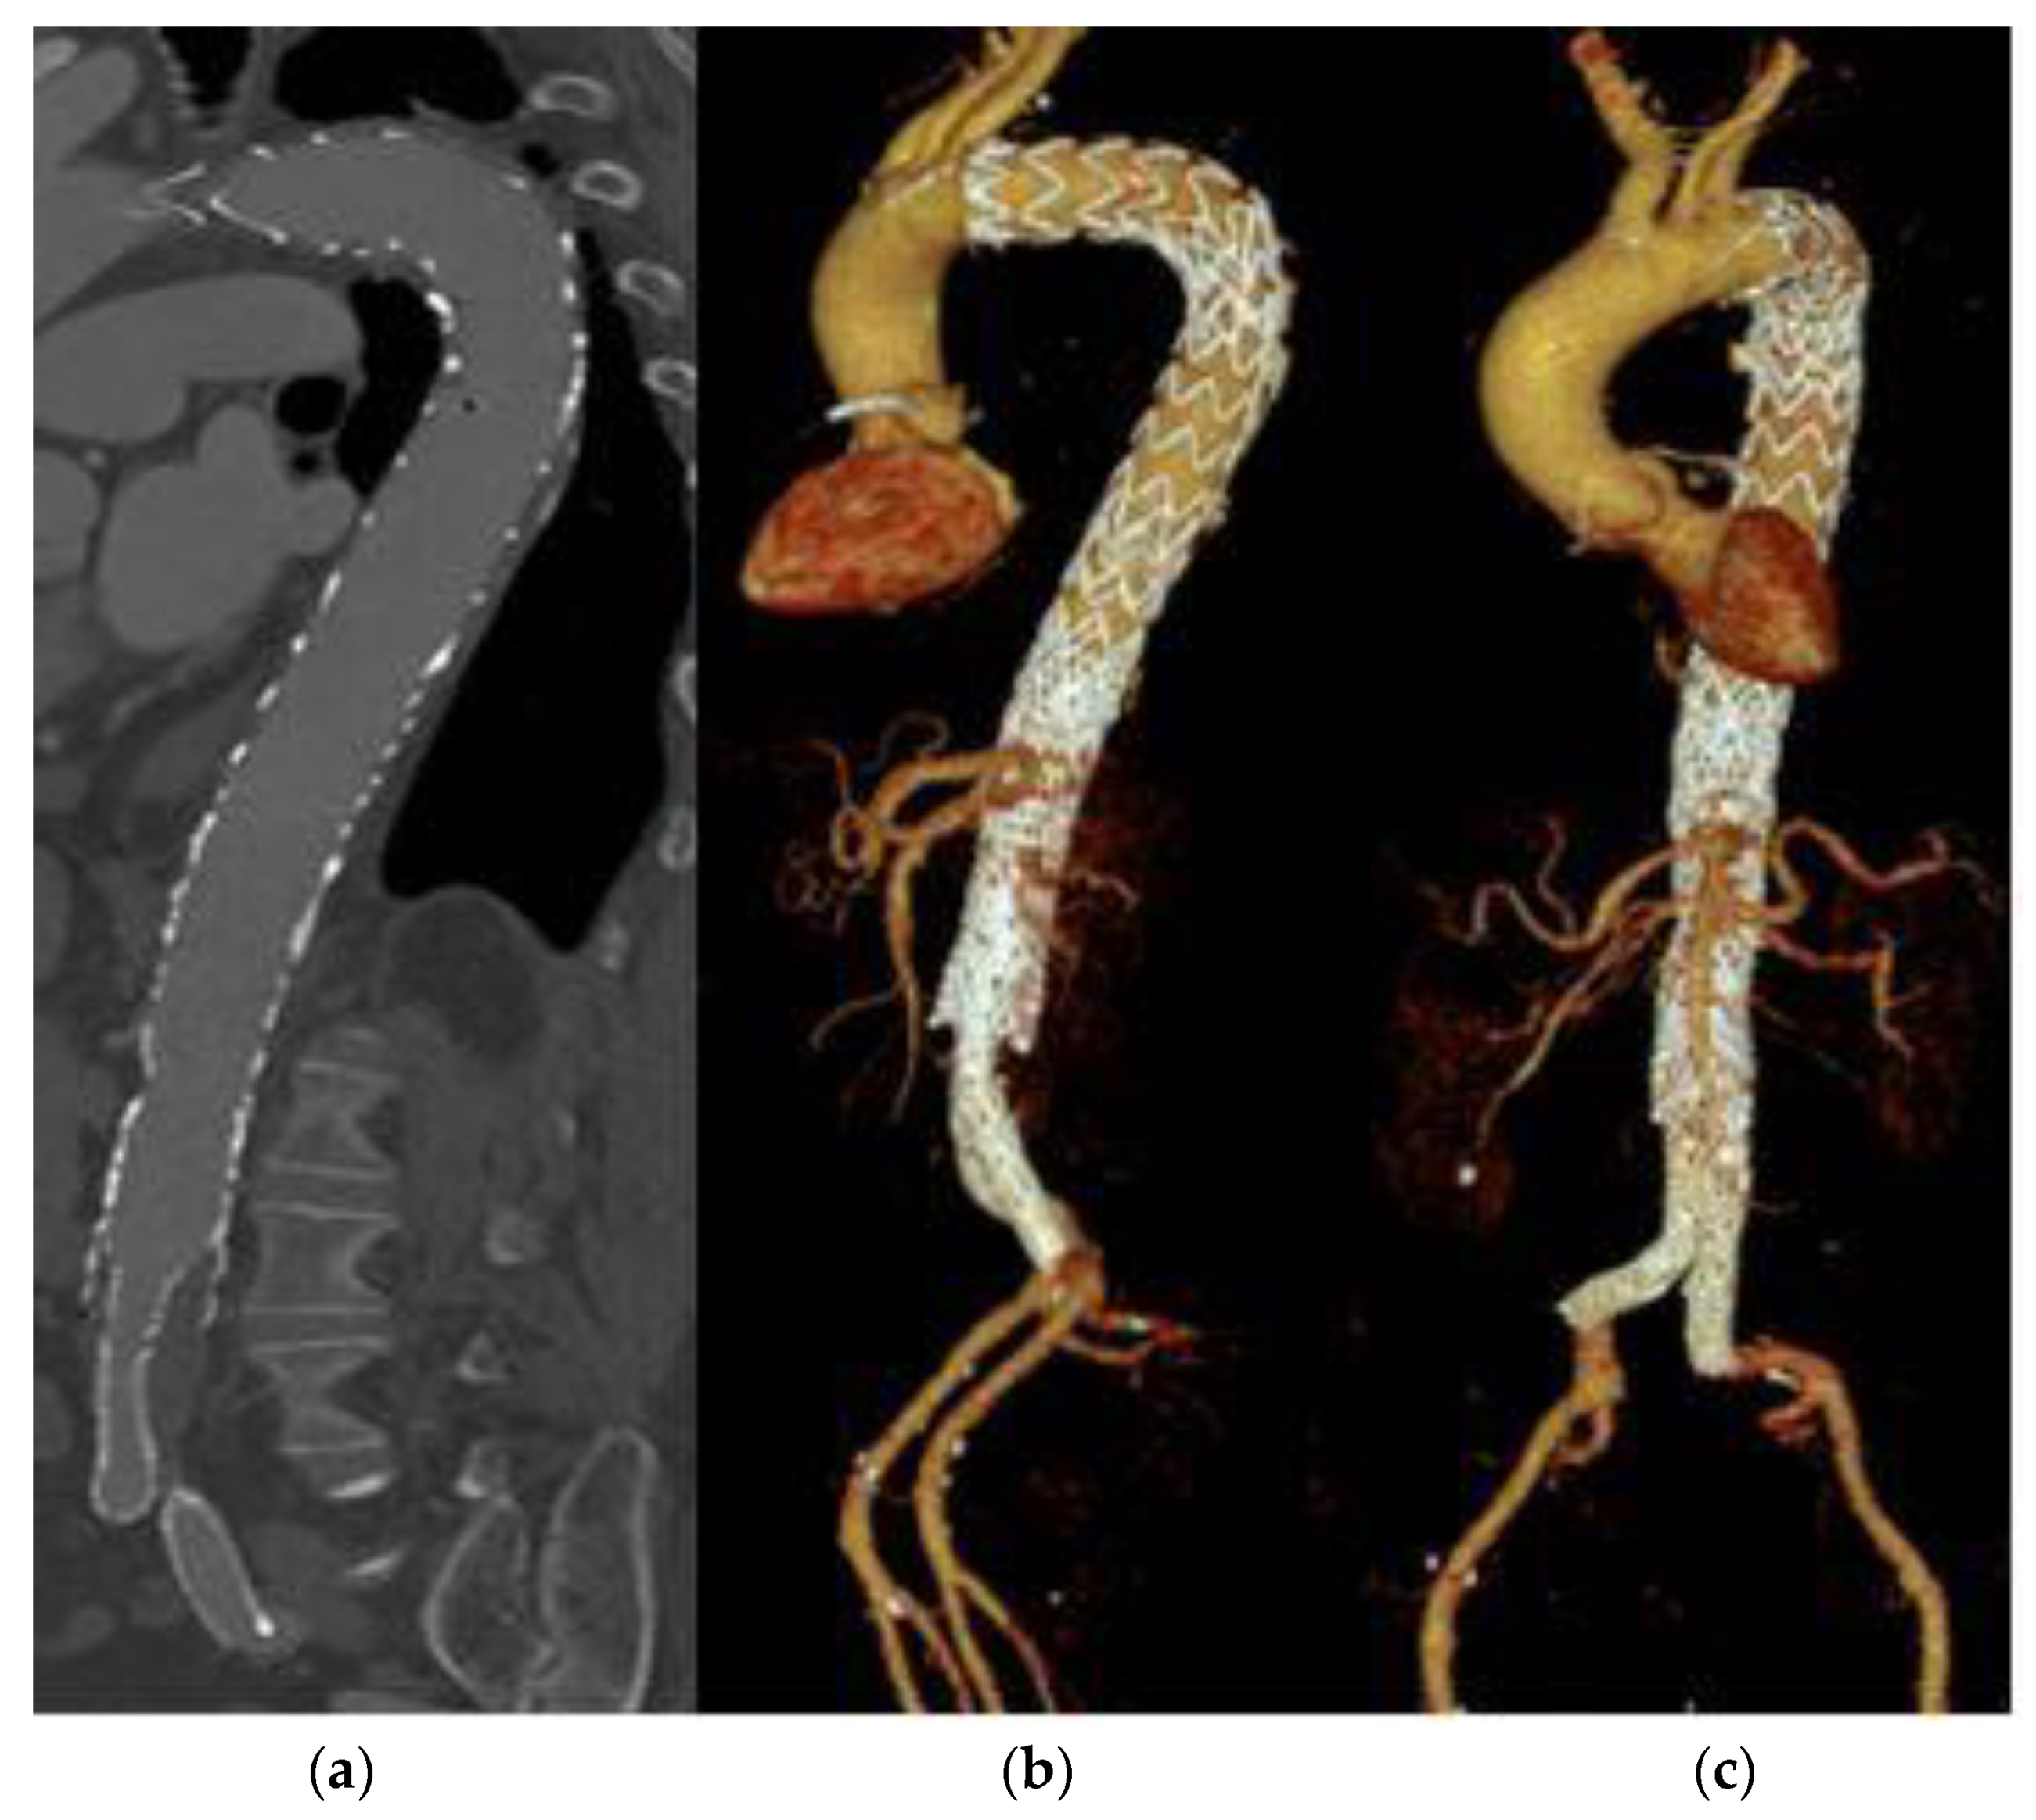

3.5. Reinterventions